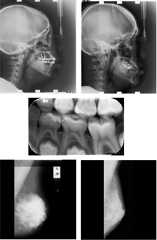

It is shown that using small sample size, denoising autoencoders constructed using convolutional layers can be used for efficientDenoising of medical images.

Figures and Tables from this paper